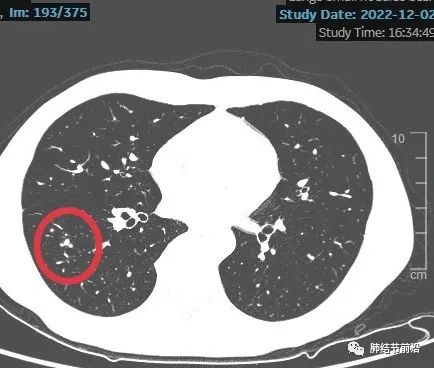

患者口服头孢治疗2周,后三个月复查来诊。薄层CT显示,右下肺磨玻璃结节变成了相邻的数枚实性小结节。

另外,CT显示为靠近胸膜,斑斑点点的相邻病灶,不符合结核卫星灶,符合隐球菌感染表现。

查血液隐球菌抗原阳性,1:40

新型隐球菌肺炎诊断明确,无需鉴别,患者免疫功能正常,给予氟康唑口服治疗。